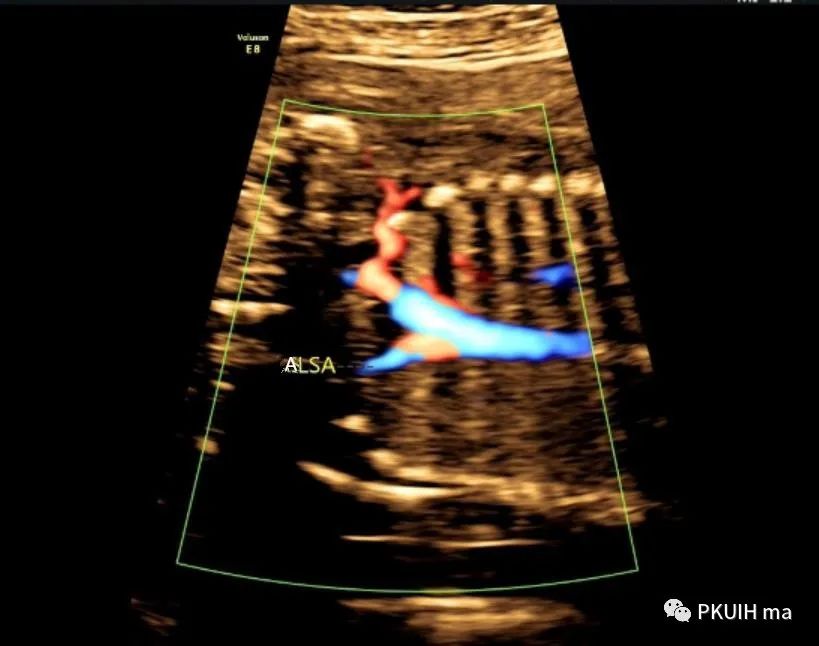

冠状切面显示右锁骨下动脉起于主动脉弓降部(ARSA:迷走的右锁骨下动脉,LSA:左锁骨下动脉)

主动脉弓走行于气管的右侧,与左位的动脉导管形成“U”型环(不完全血管环),包绕气管和食管。主动脉冠状切面可见左锁骨下动脉起自于主动脉弓降部,向左肩部走行。